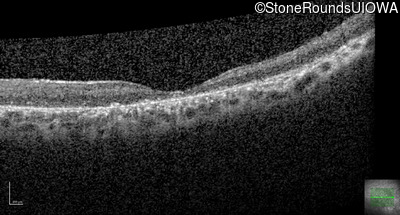

Age at visit: 41 years

This 41 year old man first came to medical attention at age 18 months when exotropia and amblyopia of his right eye were discovered. At age 11 vitreous strands and retinal vascular sheathing were seen. He has had poor night vision and constricted visual fields since his late teens. Later, at age 44 a traction retinal detachment was noted in his left eye and was treated with a scleral buckle.